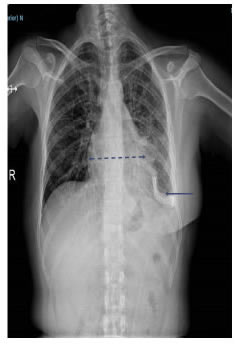

En la radiografía de tórax se observó derrame pleural izquierdo y aumento del tamaño de la silueta cardiomediastínica (figura 9).En la TC de tórax se apreciaba derrame pericárdico, con tabiques, derrame pleural izquierdo, y engrosamiento pleural y pericárdico (figura 10).

Figura 8.

Estudio citológico del derrame pericárdico maligno: se observa un fondo hemorrágico (flecha

corta) con abundantes células neoplásicas que forman mórulas y rosetas (flecha larga). Tienen citoplasma

amplio y núcleos grandes y pleomorfos. Diagnóstico citológico de líquido pericárdico: carcinoma. Tinción

de Papanicolaou, 40X.